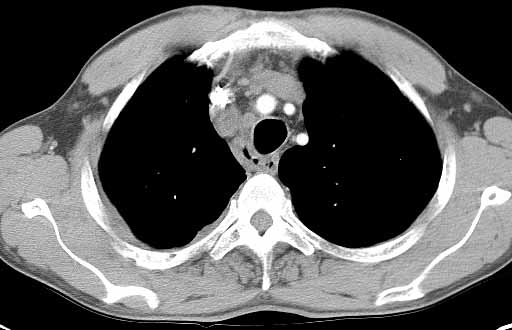

Pleurisy (PLOOR-i-see) is an inflammation * of the membrane * that covers the lungs and lines the chest cavity. The lining is called the pleura (PLOOR-a).

In pleurisy, the membrane covering the lungs and lining the chest cavity becomes inflamed, and excess fluids may build up in the space. When people who have pleurisy breathe in or cough, the inflammation causes pain, which is a result of friction from the inflamed pleura. The pain is a sharp, stabbing pain that begins suddenly. There are a number of different causes of pleurisy.